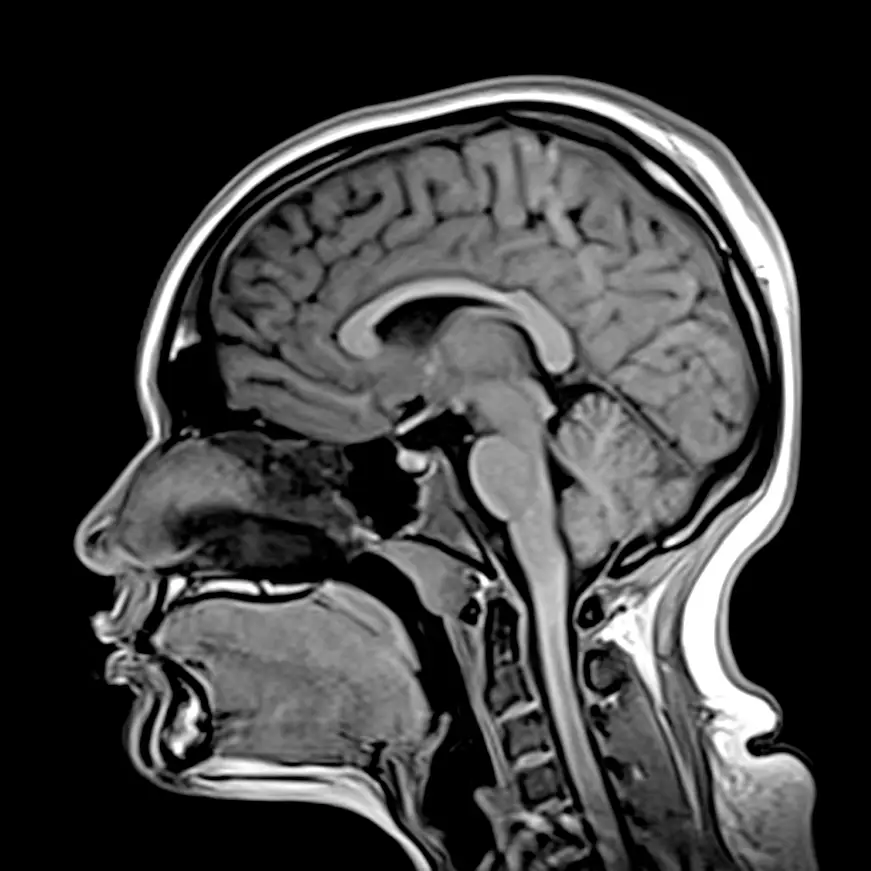

RMN de Rodilla

Rodilla